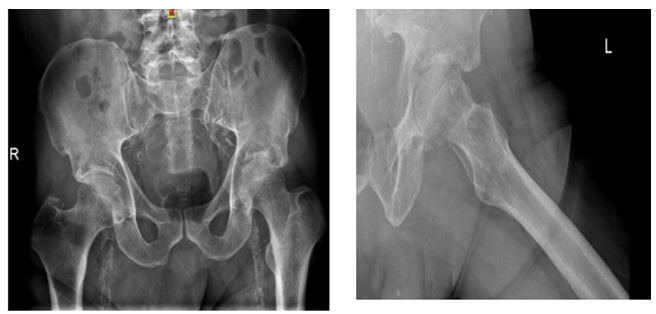

Two stage treatments consisted in an initial surgery through a posterior approach, debridement of inflammatory tissues, neck osteotomy and acetabular reaming adding a temporal non-articulated antibiotic impregnated cement spacer for the resected femoral head. 6 weeks after surgery when intravenous antibiotic treatment was completed and laboratory inflammatory parameters were controlled, a second stage surgery was planified: Conversion to a hybrid arthroplasty for the first case and a non cemented total hip arthroplasty for the second case (Figure 1) (Figure 2).

Figure 1: 60 year old diabetic male patient. A and B Plain X rays showing the narrowing of the hip joint, consequent to a psoas absess. C, D are MRI images showing the acetabular edema and sinovytis associated to psoas edema. E and F postoperative arthroplasty x-ray. Differed anatomy showed chronic inflammation compatible with osteomielitis but no germs were isolated in the cultures. Harris Hip score was 94 at 2 year follow up, infection markers controlled and no complications were reported.